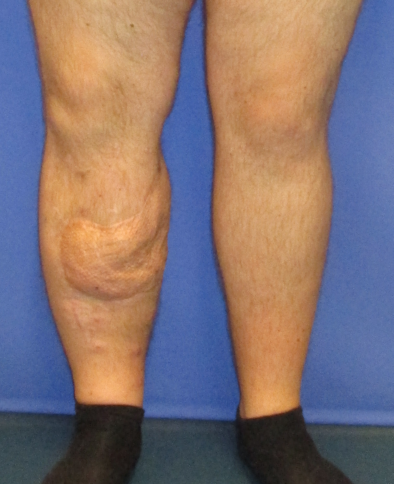

The patient underwent early physiotherapy for remobilization. Customized compression garments were worn for 6 weeks for flap remodeling. He was discharged to outpatient care on the 63rd day in a healthy condition with good scarring. The initial care was performed by the outpatient unit with weekly follow-up visits and short-term visits after 2 and 8 weeks (Figure 4 [Fig. 4] and Figure 5 [Fig. 5]), 6 months (Figure 6 [Fig. 6] and Figure 7 [Fig. 7]) and 1.5 years post-surgery (Figure 8 [Fig. 8] and Figure 9 [Fig. 9]). Given full weight bearing, the patient did not complain of any disturbance. A contrast CT performed at week 16 post discharge confirmed the efficacy of the AV loop (Attachment 1 [Att. 1]). Figure 5 [Fig. 5], Figure 6 [Fig. 6], Figure 7 [Fig. 7] and Figure 8 [Fig. 8] show the patient standing and able to walk with no crutches. The X-rays (Figure 10 [Fig. 10]) one year after bone fixation showed no sign of bone infection or pseudarthrosis after removal of the external fixator. No further surgical procedures were performed due to good overall patient satisfaction and adequate aesthetic outcome.

Figure 8: Postoperative result after 1.5 years, frontal view

Figure 9: Postoperative result after 1.5 years, lateral view